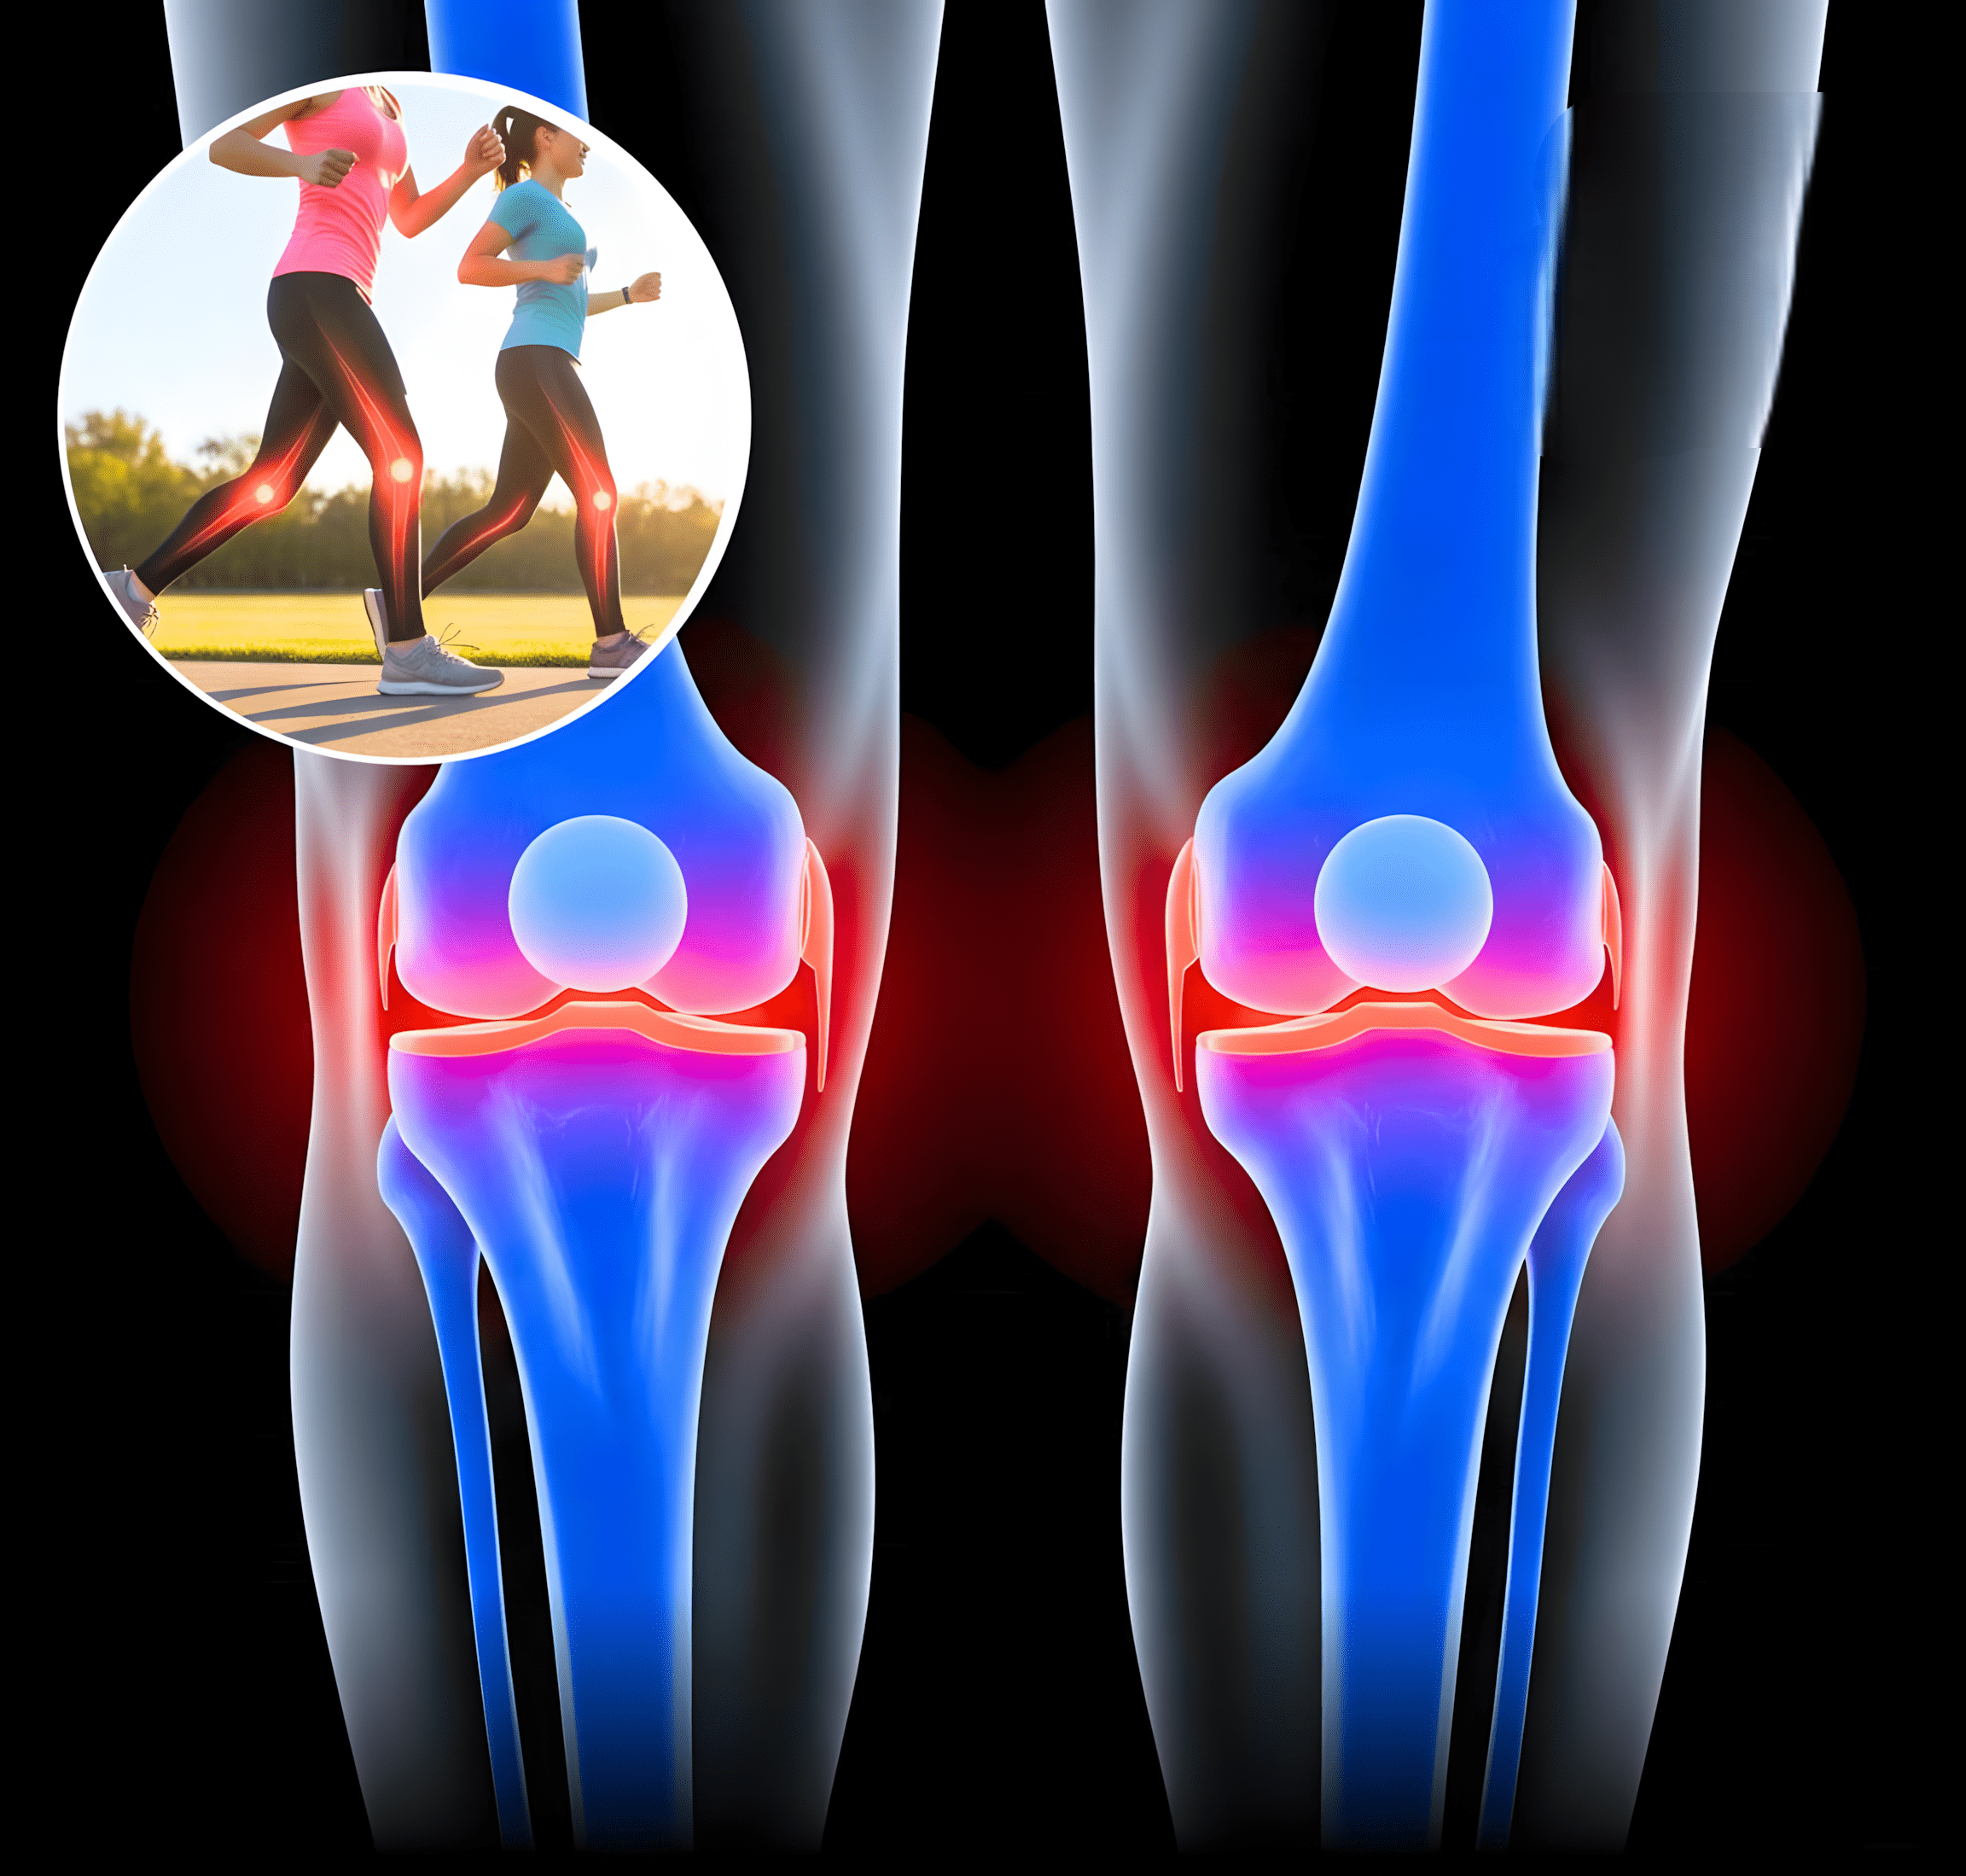

Wist je dat iets eenvoudigs als dagelijks wandelen een krachtig wapen is tegen artrose? Volgens een studie gepubliceerd in Arthritis & Rheumatology kan het zetten van meer dan 6000 stappen per dag de degeneratie van het kniekraakbeen aanzienlijk vertragen – vooral bij mensen die een verhoogd risico lopen op knieartrose.

🦴 Wat gebeurt er in je knieën tijdens het wandelen?

Elke keer dat je wandelt, gebeurt er meer dan je denkt:

Betere gewrichtssmering: Wandelen bevordert de aanmaak van synoviale vloeistof, die fungeert als smeermiddel voor je gewrichten.

Verhoogde bloedtoevoer: Het stimuleert de bloedcirculatie in en rond het kniegewricht, wat essentieel is voor de voeding van het kraakbeen.

Sterkere spieren: De spieren rondom het kniegewricht worden getraind en verstevigd, waardoor de druk op het kraakbeen afneemt.

Meer stabiliteit en mobiliteit: Sterkere spieren en beter gesmeerde gewrichten leiden tot soepeler bewegen en minder kans op blessures.

📊 De kracht van 6000 stappen: wat zegt de wetenschap?

In het onderzoek analyseerden wetenschappers het verband tussen fysieke activiteit en kniegezondheid. Hun bevinding:

▶️ Mensen die gemiddeld 6000 of meer stappen per dag zetten, hadden aanzienlijk minder kraakbeenslijtage en rapporteerden minder pijn en betere mobiliteit.

▶️ Zelfs bij mensen met overgewicht of beginnende artrose bleef dit beschermende effect meetbaar.